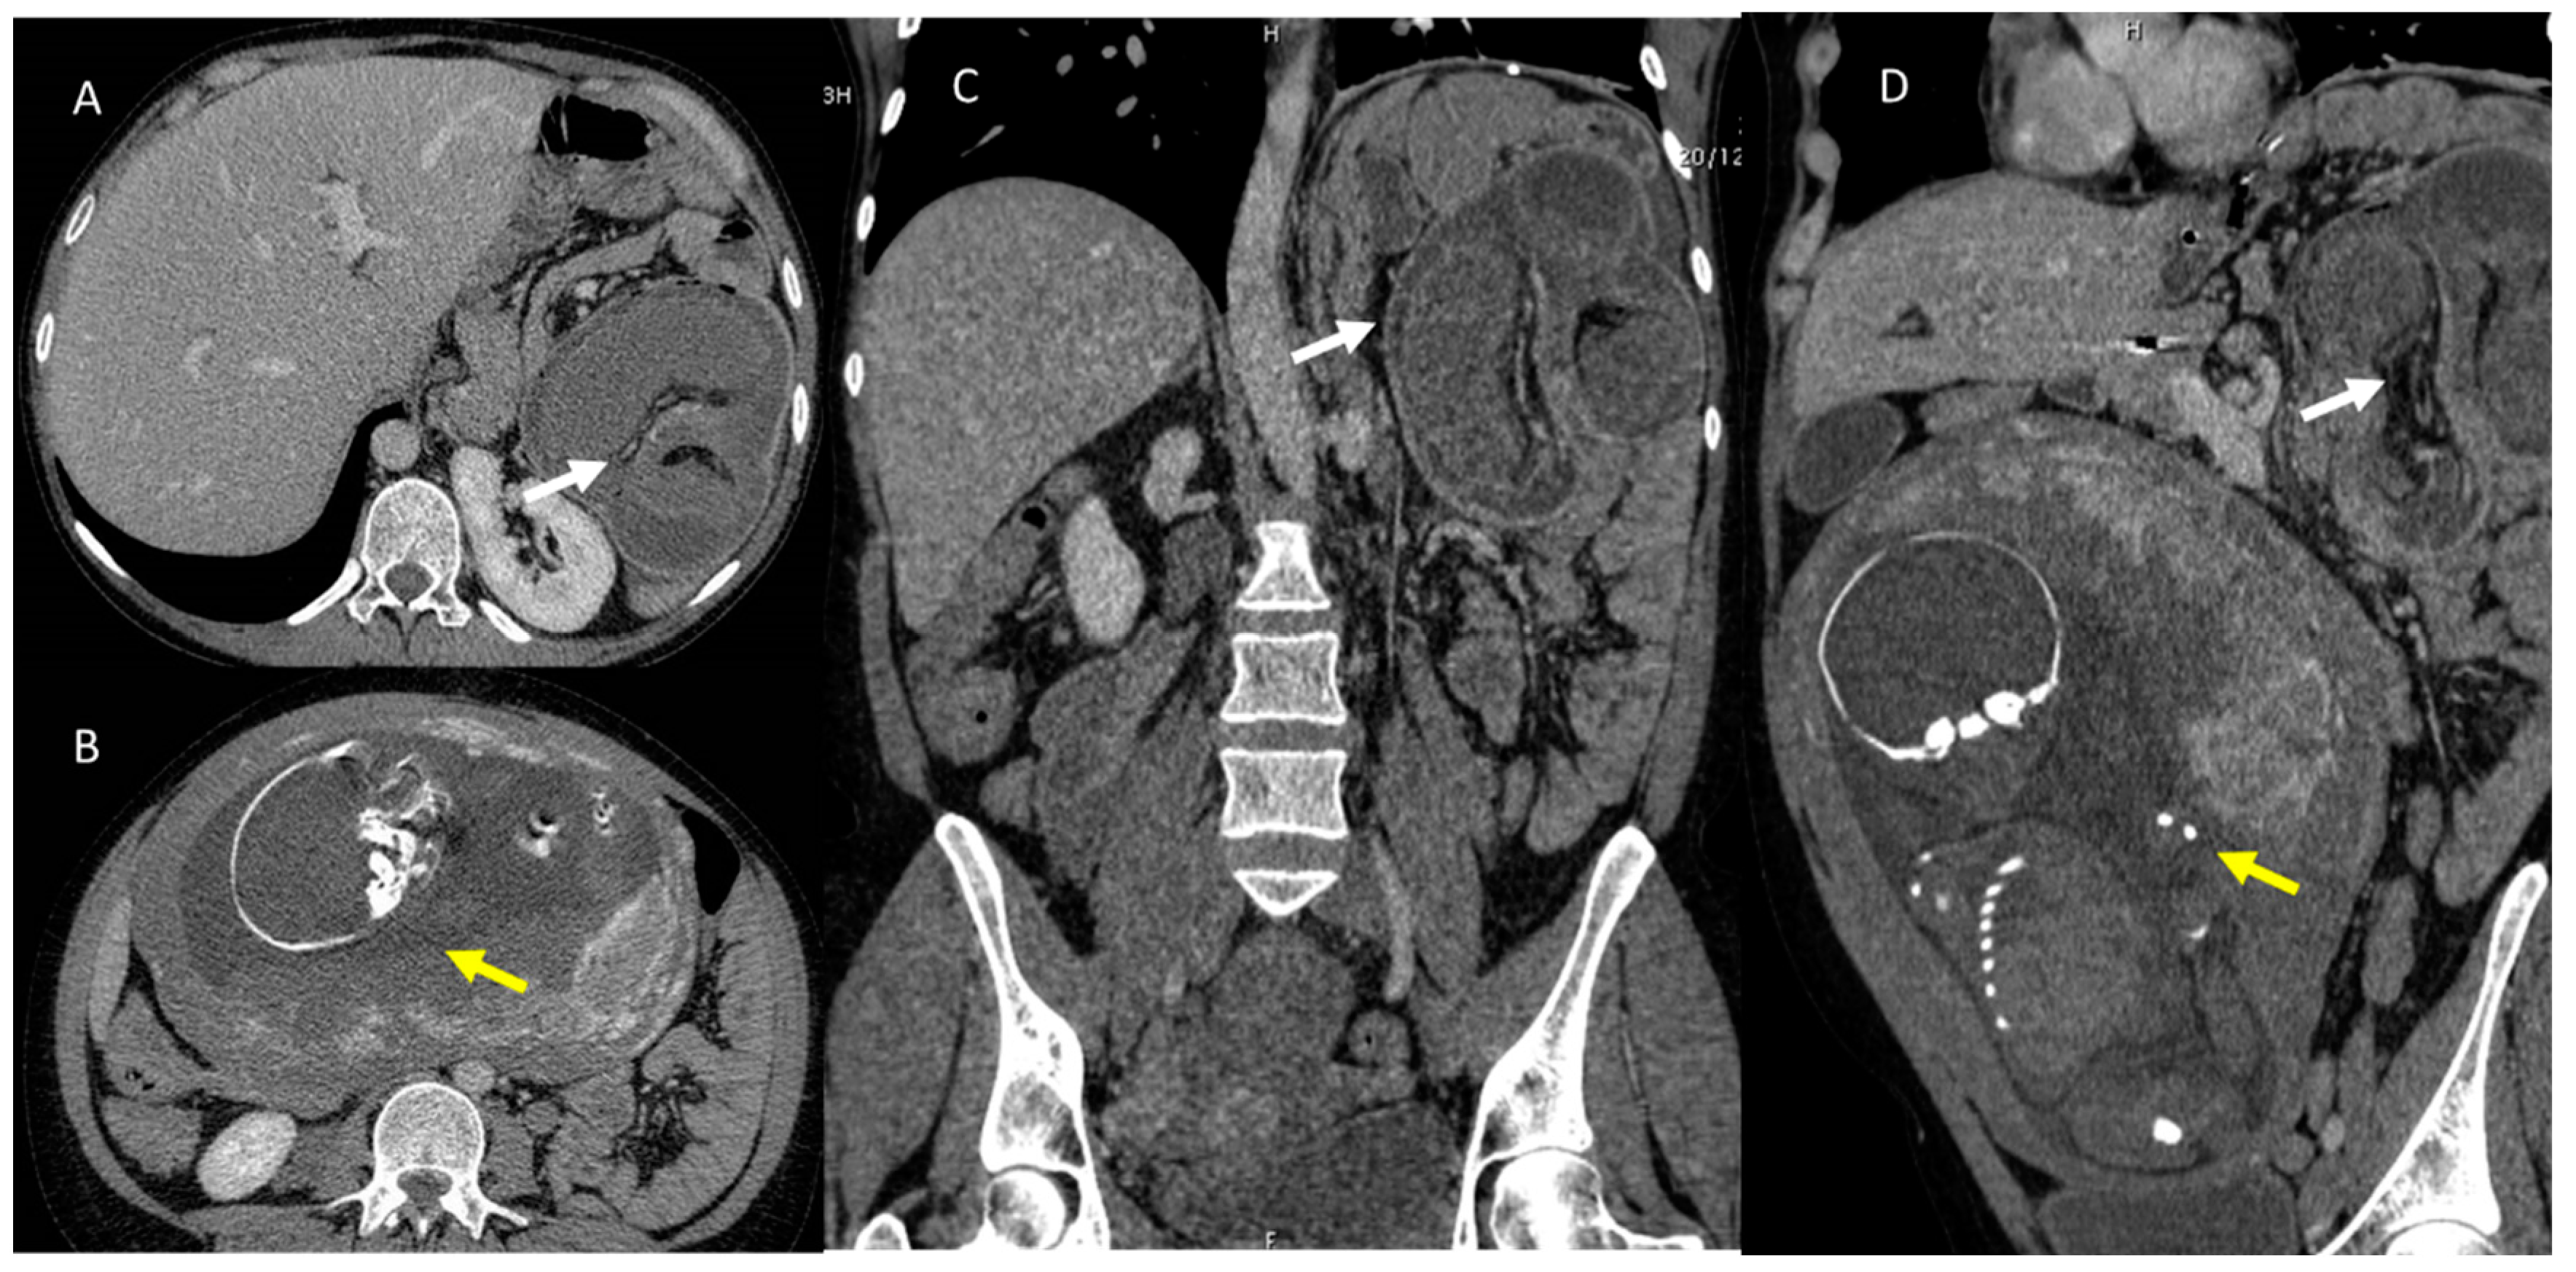

Figure 1.

Pregnant woman (yellow arrows) with emergency room admission for abdominal pain, vomiting, and heart rhythm disturbances. US assessment reveals no specific findings. CT study in axial plane (A,B) and in coronal MPR plane (C,D) shows volvulus (white arrows) of the small bowel in the left epigastrium.